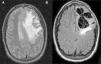

Presentamos el caso de un varón de 23 años, alérgico a penicilinas, sin otros antecedentes clínicos ni tóxicos salvo haber presentado una infección de vías respiratorias altas 14 días antes. Es llevado al Servicio de Urgencias por episodio de desconexión del medio, ausencia de emisión de lenguaje y convulsiones tónico-clónicas con relajación de esfínteres. Se encontraba hemodinámicamente estable, con temperatura de 37,2°C, una puntuación en la escala de coma de Glasgow de 11 (apertura ocular 2, respuesta verbal 4 y respuesta motora 5) y hemiparesia derecha. Analíticamente destacaban 16.420 leucocitos/μl con neutrofilia del 95%. En la tomografía computarizada (TC) craneal de urgencia se observaba una lesión hipodensa subcortical frontal izquierda, que no captaba contraste, con efecto masa que colapsaba parcialmente los ventrículos laterales y desplazaba 8mm la línea media. Ingresó en el Servicio de Neurocirugía con el diagnóstico de probable glioma de bajo grado. Se completó el estudio con resonancia magnética (RM) cerebral en la que se confirmaba la existencia de una lesión hiperintensa no captante, que ocupaba el lóbulo frontal izquierdo con extensión al lóbulo parietal y cuerpo calloso con signos de herniación subfalcial (fig. 1A). El comienzo de fiebre con un pico de 38,2°C hizo sospechar la posibilidad de encefalitis vírica y se comenzó de manera empírica tratamiento con aciclovir y posteriormente se amplió con cobertura antibiótica consistente en aztreonam, metronidazol y linezolid. Debido a un rápido deterioro del nivel de consciencia que presentó el paciente, se trasladó a la Unidad de Cuidados Intensivos (UCI) y una vez estabilizado se intervino de urgencia mediante craniectomía descompresiva encontrándose un tejido friable y muy edematizado, con signos de hipertensión intracraneal, pero sin lesiones corticales que sugirieran lesión tumoral. Se enviaron muestras tanto de líquido cefalorraquídeo (LCR) como de tejido encefálico a los laboratorios de Microbiología y Anatomía Patológica. El postoperatorio trascurrió en la UCI con escasa mejoría, persistiendo la afasia y rigidez de miembros. En el control por RM aunque había disminución de la desviación de la línea media, se mantenían lesiones hiperintensas residuales (fig. 1B). Las serologías de VIH, virus herpes, Mycoplasma sp. y Chlamydia sp. resultaron negativas, así como la reacción en cadena de la polimerasa (PCR) para virus neurotropos (virus herpes tipo 1 y 2, varicela zóster, citomegalovirus, virus de Epstein-Barr y virus Toscana) y cultivos microbiológicos de las muestras de tejido cerebral. Los hallazgos de la histopatología del tejido resecado mostraban importante hemorragia perivascular e infiltrado neutrofílico y macrofágico de las vainas perivasculares de arteriolas y capilares junto a desmielinización marcada, siendo compatible con el diagnóstico de LAH (enfermedad de Weston-Hurst). El paciente se trató inicialmente con bolos de 1g de metilprednisolona durante 5 días y al no haber mejoría se inició terapia con plasmaféresis, realizándose 7 ciclos, presentando una evolución favorable a estos últimos.